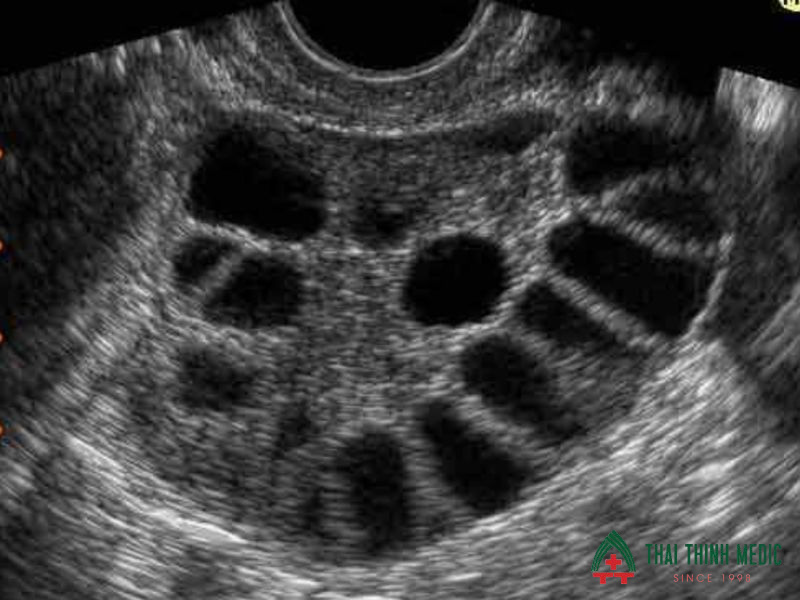

Hội chứng buồng trứng đa nang

Hội chứng buồng trứng đa nang là một rối loạn nội tiết thường gặp ở phụ nữ trong độ tuổi sinh sản. Bệnh có thể gây ra các triệu chứng như rối loạn kinh nguyệt, khó mang thai, tăng cân hoặc mọc nhiều lông trên cơ thể. Tuy nhiên, không phải ai mắc bệnh cũng có biểu hiện rõ ràng.

Siêu âm phụ khoa đóng vai trò quan trọng trong việc hỗ trợ chẩn đoán hội chứng buồng trứng đa nang. Trên hình ảnh siêu âm, bác sĩ có thể thấy nhiều nang nhỏ xuất hiện ở buồng trứng, tạo thành hình ảnh đặc trưng của bệnh.

Phát hiện sớm hội chứng buồng trứng đa nang giúp phụ nữ có hướng điều trị kịp thời, cải thiện sức khỏe sinh sản và giảm nguy cơ vô sinh.

- Quan sát số lượng nang nhỏ trong buồng trứng

- Đánh giá kích thước và cấu trúc buồng trứng

- Phát hiện sự thay đổi bất thường trong quá trình rụng trứng

- Hỗ trợ chẩn đoán rối loạn nội tiết liên quan đến sinh sản

- Theo dõi hiệu quả điều trị và khả năng sinh sản

Buồng trứng đa nang